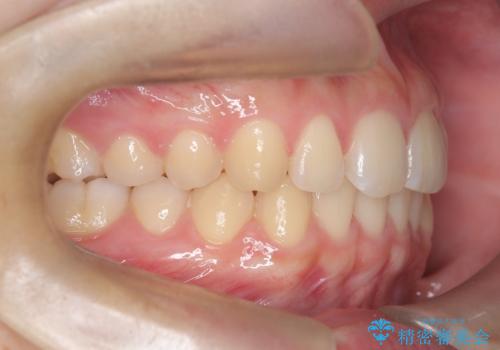

マウスピース矯正で前歯のガタツキを改善! 短期間で治療完了

- 前歯のガタツキが気になるとのことで来院されました。

マウスピース矯正で治療することとしました。